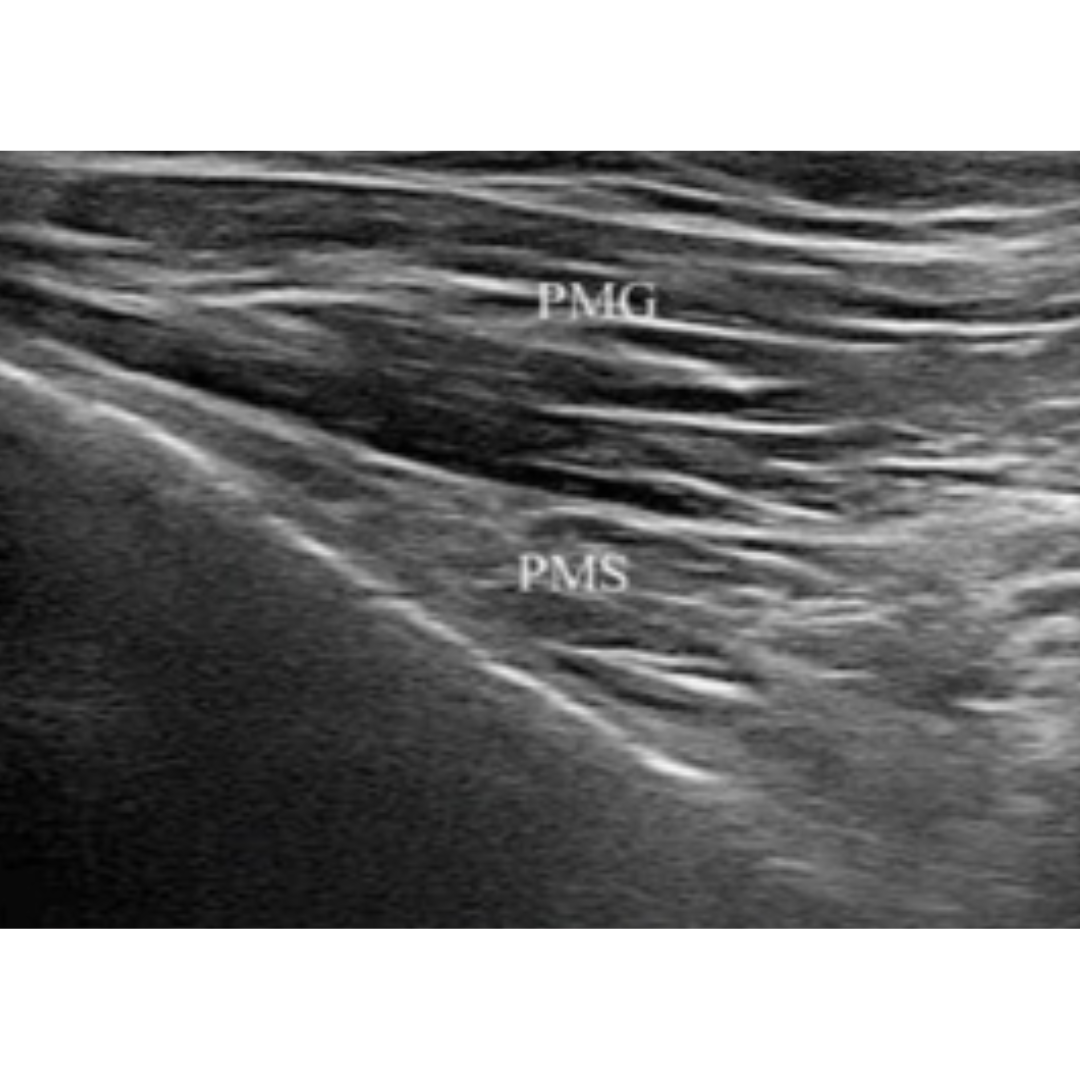

Imagen 2: Corte transversal. : músculo pectoral mayor(PMG) y músculo pectoral meno (PMS)